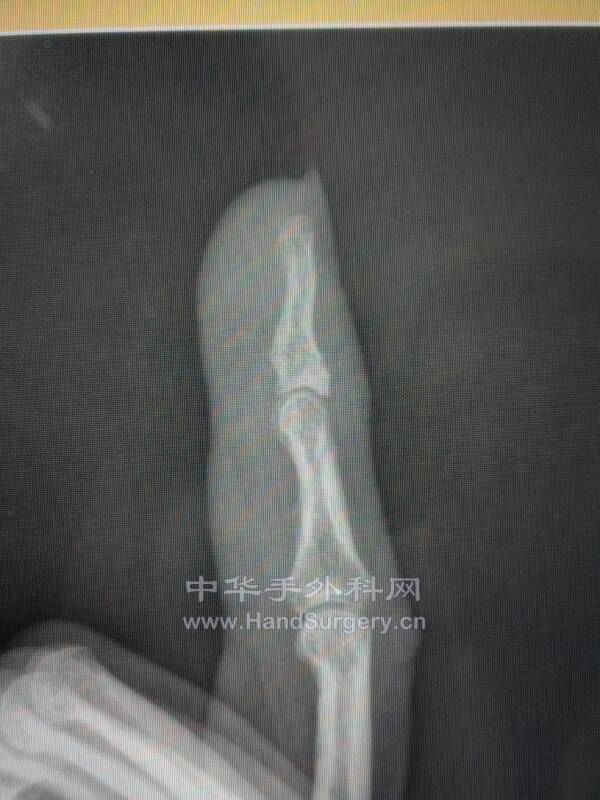

手外科医生太辛苦科里一共4个人值班,骨折了还一直在值班做手外科急诊手术

知道骨折了,准备来天津找我手术